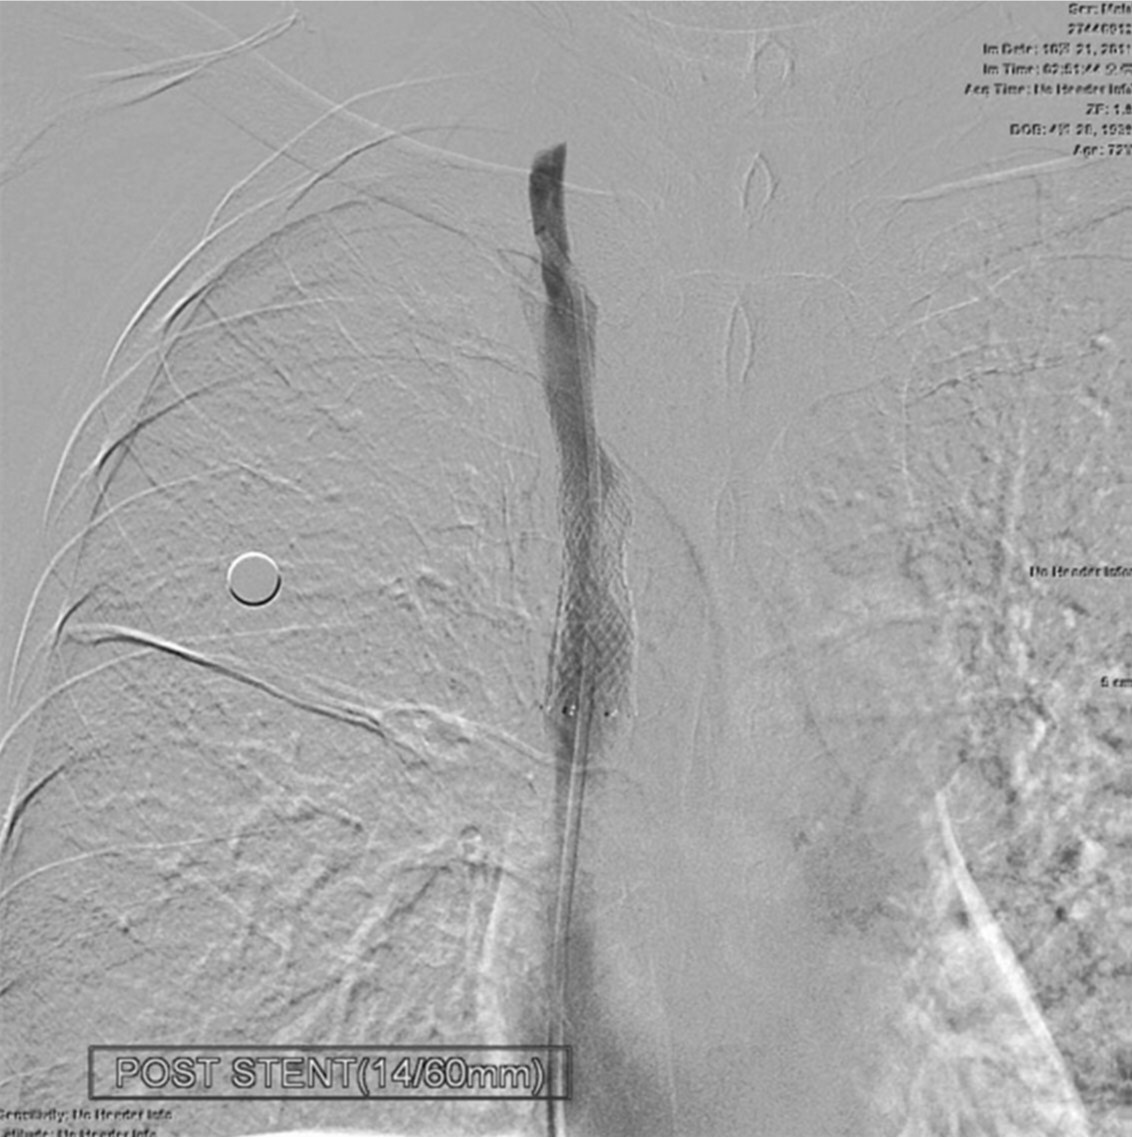

Fig. 4.

Fig. 4. After placing the self-expanding stent, the stenotic segment was dilated with a balloon catheter.